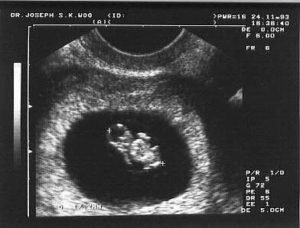

Personhood is an idea used only when we want to deny someone their humanity. The pro-choice argument of when someone is or is not a person is used to differentiate a child in the womb from one outside the womb. We covered these differences in the previous article, but there should also be something said about the general idea of personhood. Whenever personhood has been tied to anything more restrictive than a human being, it has always had a sinister purpose. To call someone less than a person is to deny them rights that should be afforded everyone. Sadly, it is not a new tactic even if the language has changed. In the US, it was used against Native Americans and African-Americans for many atrocities. History is full of many more examples. We must understand that the only purpose for denying someone personhood is to assert control over them that is not for their benefit.